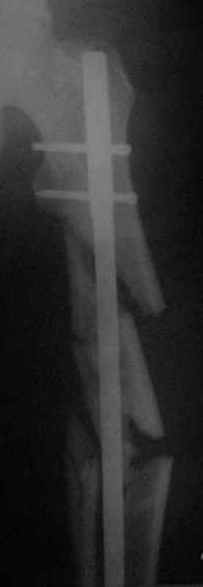

Здравствуйте коллеги! 10.07.2006 года поступил молодой человек 26 лет с Диагнозом:

Открытый (2 В Каплан) многооскольчатый перелом левого бедра. Перелом межмыщелкового возвышения большеберцовой кости без смещения слева. Открытый (1 А Каплан) перелом с/3 -н/3 костей правой голени, перелом пяточной кости справа. На седьмые сутки выполнены операции:1. ЗИМО (статически, Chm-CHARFIX) левого бедра. 2. Остеосинтез стержневым аппаратом костей правой голени и пяточной кости. См. r-gr. На сегодня аппарат демонтирован, больной ходит с ограниченной нагрузкой. Смущает стояние отломков в верхней трети бедра (как то не задумались при планировании операции о реконструктивном или гамме штифте ) хватит ли этих двух винтов для стабильности? С Уважением Владимир Бахарев.